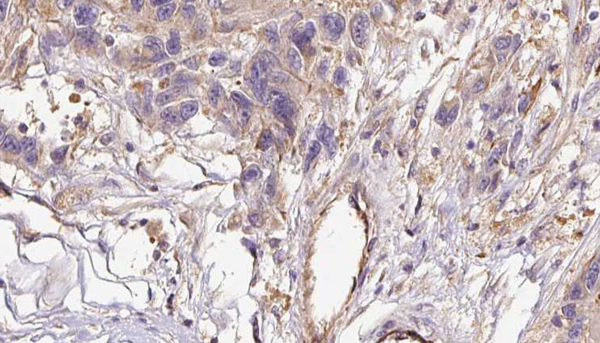

IHC (Immunohistochemisry)

(AAA323015 at 1/100 staining Human liver cancer by IHC-P. The sample was formaldehyde fixed and a heat mediated antigen retrieval step in citrate buffer was performed. The sample was then blocked and incubated with the primary Ab at 4°C overnight. An HRP conjugated anti-Rabbit Ab was used as the secondary Ab.)